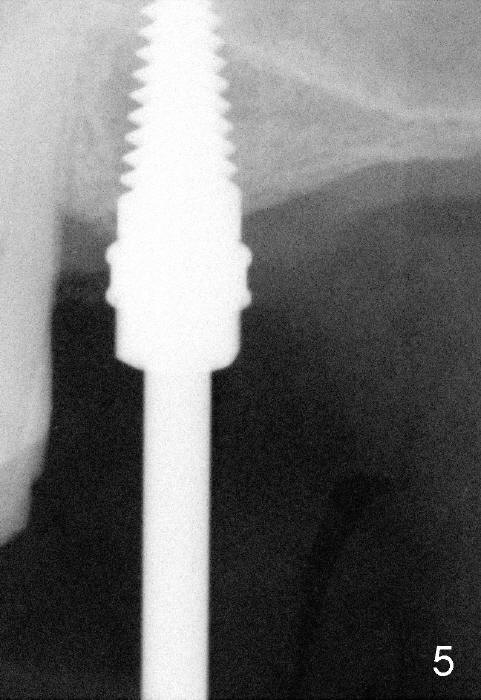

To solve the dilemma, 4.5x11 mm tap is placed by a wrench at the depth of 8

mm. So an adapter is required. Hand placement of the tap is more

controllable than handpiece's in term of trajectory (Fig.5, 5'). Although hand

placement of the tap is slower, it gives us time to watch whether the buccal

plate is fracturing or not. The depth is also controlled better

(intentional sinus lift without bone graft). Finally 4.5x11 mm implant is